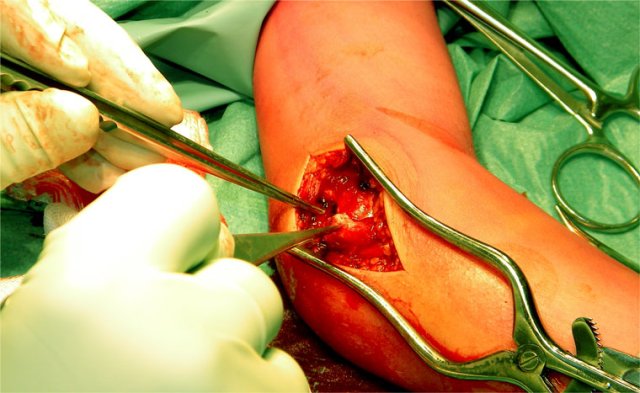

The case on the left shows a lateral condyle fracture extending through the ossified part of the capitellum.

This is a Milch I fracture. The elbow is stable.

There is too much displacement so osteosynthesis has to be performed.

MRI can be helpfull in depicting the full extent of the cartilaginous component of the fracture.